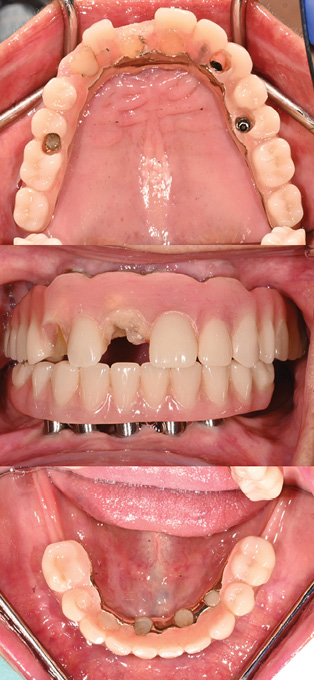

2. Retread: Utilizing existing reference

76y/o male ASA II patient presents seeking repair of fractured teeth #12, 11, 21 on maxillary hybrid IS-FDP

Clinical examination:

- Extraoral examination: Apparent loss of VDO (downturned lips, angular cheilitis, closest speaking space)

- Intraoral examination: Heavily worn teeth with framework visible, history of repeated fractures, no nightguard usage

- Opposing dentition: Mandibular IS-FDP

– Prostheses age: 25 years (framework fabricated in 1999)

- Last retread: 7 years (2017)

- Repaired 4 times since 2020

- Existing master casts with implant analogs and models of prostheses after last retread

– Treatment provided: retread of maxillary and mandibular IS-FDP

Sequence of appointments (Figs. 3-5):